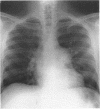

A 31 year old man presented with a left hilar mass. Thoracic tomography showed this mass to be the pulmonary artery, and subsequently idiopathic dilatation of the pulmonary artery was diagnosed. He remained well until 11 years later when he died suddenly. Postmortem examination confirmed idiopathic dilatation of the pulmonary artery with death due to pulmonary artery dissection and cardiac tamponade. It seems likely that idiopathic dilatation of the pulmonary artery predisposed to fatal pulmonary artery dissection.